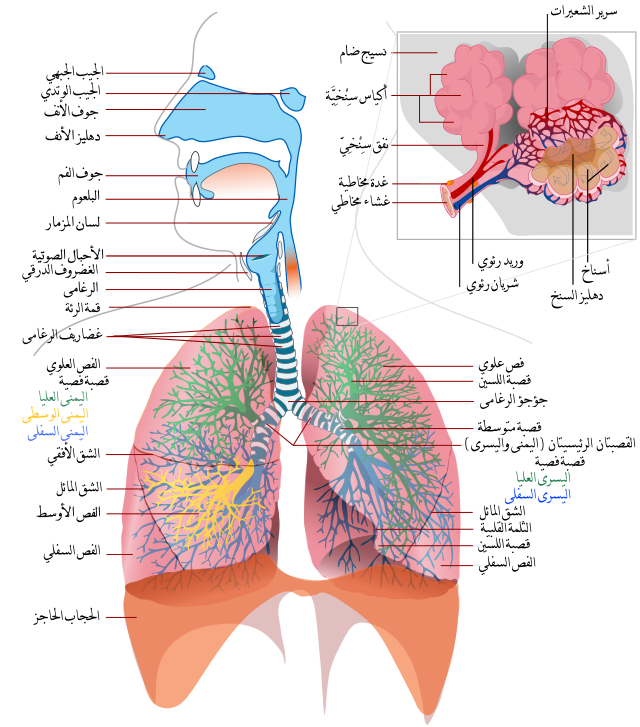

هنالك عدّة طرائقَ لشرح كيف يؤثّر البرد سلبيًّا على الجسم: عندما نبرُدُ، ينخفِضُ تدفّقُ الدَّم إلى أعضاء الجسم، وهذا يصعّب على جهاز المناعة العملَ بِصُورتِهِ المثلى. أضِفْ إلى ذلك أنّهُ في شُروط البرد والجفاف، تَجِفُّ مخاطيّة الأنف، وتَظهرُ صعوبةٌ في منع دخولِ الأمراض عن طريق الأنف، وهكذا تضعُفُ المقاومةُ الطّبيعيّة للجسم أمامَ الملوّثات.

جهاز التنفّس | نقلاً عن ويكيبيديا; أنتجها – يوسي